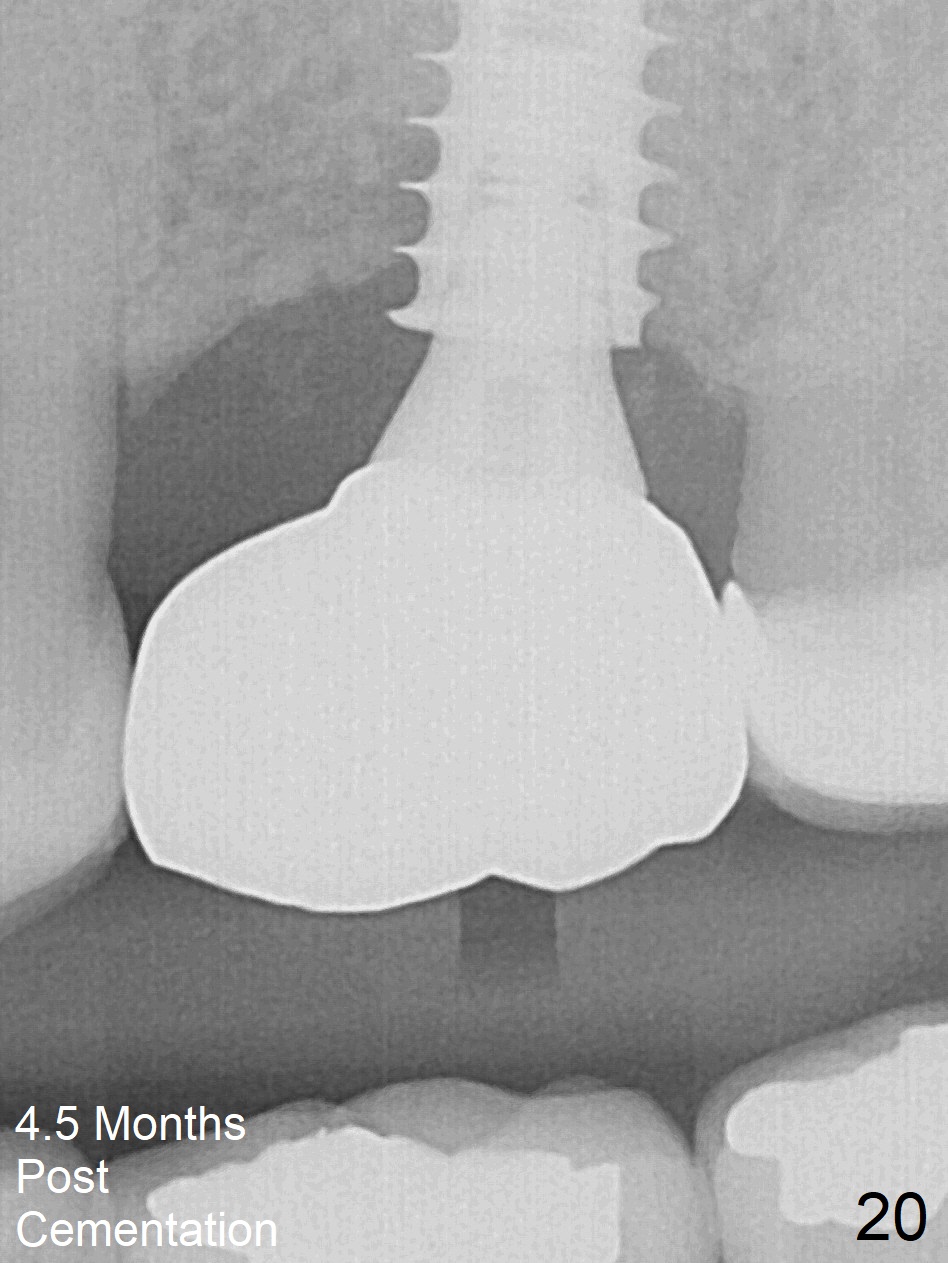

The implant is stable 8 months postop (Fig.15). When a 6x4(3) mm abutment is placed 8.5 months postop, it is distal (Fig.16). The mesiodistal width is 1-2 mm shorter than that at #3, which suggests the mesial shift of the tooth #15. A provisional is fabricated at #14 (Fig.17 P) with supra-occlusion so that there is clearance between the tooth #15 and the opposing one (Fig.18 *). With a separator placed between #14 and 15 (Fig.19), the latter is free to be distalized. Bone volume and density seem to increase 4.5 and 10.5 months post cementation (Fig.20,21, as compared to Fig.15), although the buccal plate remains as concave as shown in Fig.18. One year 5 months post cementation, the patient complains of bad smell from the implant when water pik is being used. It appears that the 1st 2-3 threads are exposed (Fig.22), although the surrounding gingiva remains uninfected. Bone graft is recommended. The site heals without bad smell 7 months post bone graft (2 years 4 months post cementation, Fig.23). The 1st implant thread is found exposed buccal on uncover (regraft?). A small healing abutment is placed because the implant is placed distal (Fig.24). An angled abutment should be tried and #15 crown will be redone. Impression will be taken when the gingiva heals around the provisional crowns.